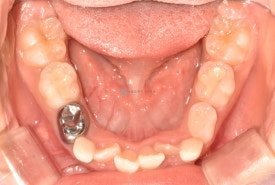

치료 전 - 위아래 심한 공간 부족이 관찰됩니다.기존 교정장치와 같은 철사 찔림이 없고 확장과 치아배열이 동시에 잘되는 투명교정장치입니다. 착용한 상태에서도 거의 티나지 않아 아이들이 좋아합니다.😁

기존 교정장치와 같은 철사 찔림이 없고 확장과 치아배열이 동시에 잘되는 투명교정장치입니다. 착용한 상태에서도 거의 티나지 않아 아이들이 좋아합니다.😁